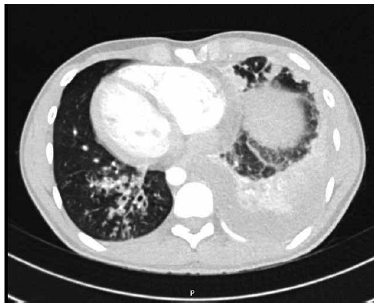

Adicionalmente, se solicitó tomografía de tórax con protocolo para tromboembolismo pulmonar el cual descartó el mismo; Sin embargo, se evidenció derrame pleural tabicado en lóbulo inferior izquierdo con opacidades alveolares e infiltrados intersticiales peribroncovasculares con engrosamiento de septos interlobulillares. Además, con bronquiectasias cilíndricas, algunas con tapón mucoso (Fig.2). Se realizó toracentesis diagnóstica con evidencia de líquido pleural exudativo, neutrofílico compatible con derrame pleural complicado (LDH >1000, Glucosa <40). Se llevó a decorticación pulmonar sin complicaciones, con estudios de PCR para Mycobacterium tuberculosis y cultivo de gérmenes aerobios y anaerobios negativos.

Figura 2 Tomografia de tórax: derrame pleural tabicado en lóbulo inferior izquierdo con opacidades alveolares e infiltrados intersticiales peribroncovasculares con engrosamiento de septos interlobulillares. Además, con bronquiectasias cilíndricas, algunas con tapón mucoso